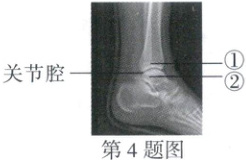

4. (2024河北16题)如图为某人左脚的踝关节射线透视图像,①②表示踝关节内的结构。下列说法错误的是 (

A.①是关节头,②是关节窝

B.①②表面覆盖着关节软骨

C.关节腔内有滑液,使关节灵活

D.踝关节在运动中起枢纽(支点)作用

A

)A.①是关节头,②是关节窝

答案:

4.A